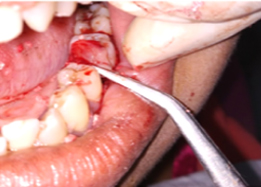

Hemisectomy

Placement of PRF Membrane